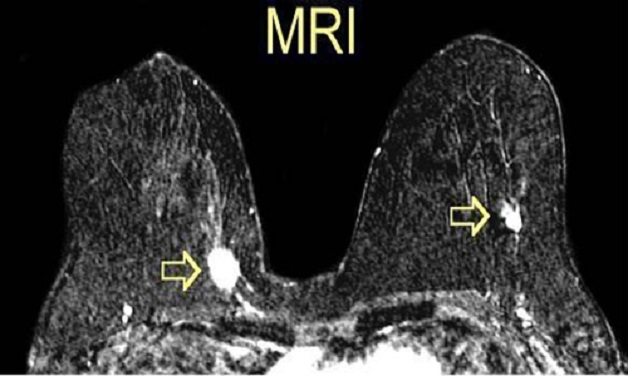

3.3. Chụp MRI tuyến vú

Phương pháp chụp cộng hưởng từ MRI cũng là kỹ thuật chẩn đoán hình ảnh hiện đại để giúp phát hiện ung thư và một số bất thường khác ở tuyến vú. Kỹ thuật này mang tới độ chính xác cao, hình ảnh sẽ được hiển thị rõ ràng để bác sĩ đưa ra kết luận chính xác cho người bệnh.

Chụp cộng hưởng từ MRI cũng là kỹ thuật chẩn đoán hình ảnh hiện đại để giúp phát hiện ung thư vú